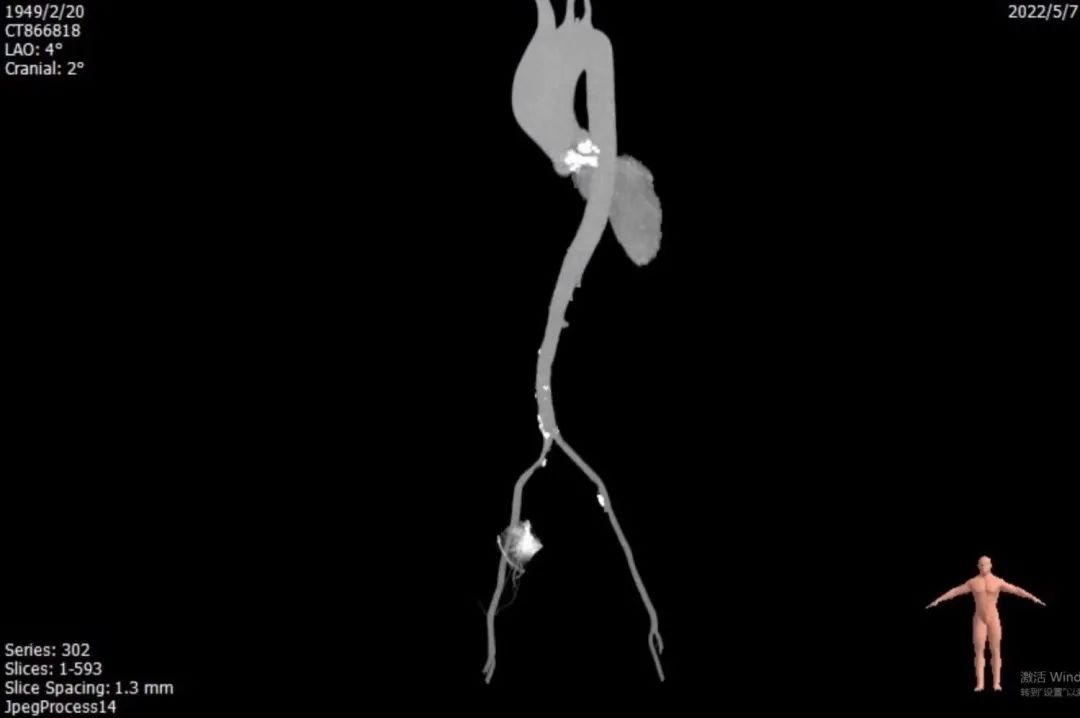

主动脉弓角度与宽度可,心脏水平夹角47°

入路血管左侧分叉高,无迂曲。左侧血管平均最小内径4.7mm,右侧血管平均最小内径4.2mm

1. 患者钙化非常严重,Type 0型二叶瓣,钙化积分高达2100+,钙化主要分布瓣叶、瓣叶交界,升主动脉严重扩张,必要时使用Snare辅助过弓和跨瓣;

2. 患者主动脉弓角度在过弓时会遇到困难,并且降主动脉明显瘤样扩张,容易产生夹层;

3. 患者入路条件不好,双侧股动脉明显狭窄,术中会采用外周预扩球囊4.0mm、5.0mm及6.0mm逐步预扩张右侧股动脉和右髂动脉,造影验证预扩后情况,根据预扩张后情况决定是否采用右侧股动脉为主入路血管;

4. 患者入路血管左侧分叉高,无迂曲。